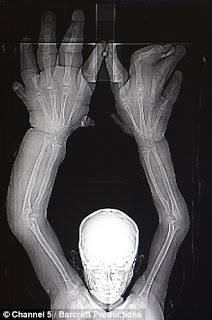

Namanya Mohammed Kaleem, seorang anak laki-laki yang tinggal di India ini memiliki kondisi tangan yang ukurannya 3 kali lipat dari ukuran normal dengan berat 8 Kg. Keadaan ini menyebabkan bocah berusia delapan tahun ini tidak bisa sekolah lantaran teman-temanya ketakutan dengan kondisi yang dialaminya.

Dalam dunia medis, kondisi tersebut dinamakan Macrodactyly atau Gigantism Local. Peristiwa ini yang jarang terjadi ini disebabkan karena pertumbuhan yang berlebihan pada bagian tertentu seperti tangan dan juga pada kaki.

Macrodactyly tidak menyebabkan gangguan fungsi tubuh yang lain, namun kondisi ini akan menyebabkan masalah psikis tersendiri bagi yang mengalaminya. Macrodactyly bukanlah penyakit keturunan yang bisa diwariskan ke generasi berikutnya. Penyebab dari penyakit ini dikaitkan dengan kondisi tertentu seperti neurofibromatosis, tuberous sclerosis dan malformasi vaskular .